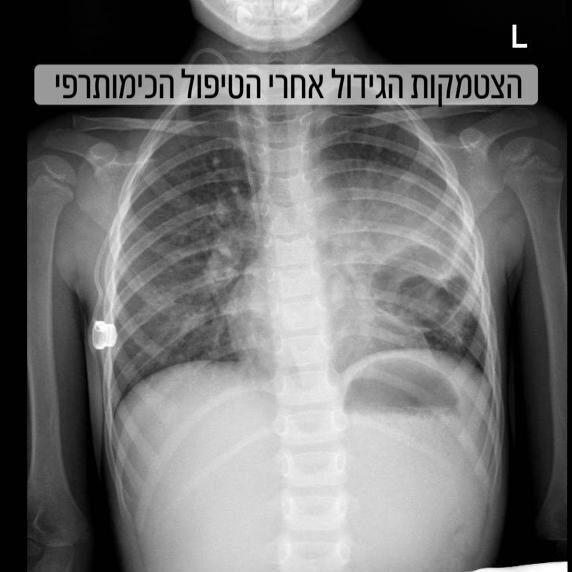

כבר לאחר הטיפול הכימותרפי הראשון נרשם שיפור נשימתי משמעותי, ולאחר שלושה טיפולים נוספים הדגימו הבדיקות כי הגידול הצטמק ביותר ממחצית מנפחו המקורי. בעקבות השיפור ולאחר הערכה רב-תחומית, הוחלט על ביצוע ניתוח מורכב וחריג.